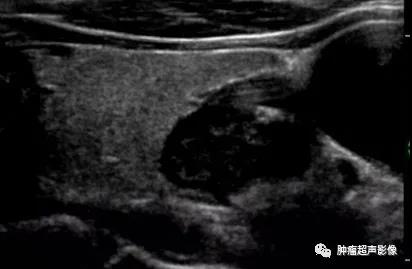

慢性肾脏疾病,血PTH升高,左侧2个(上图)、右侧1个(下图)增大的甲状旁腺腺体,呈边界清的低回声,与甲状腺分界清晰,其中两个内见钙化。